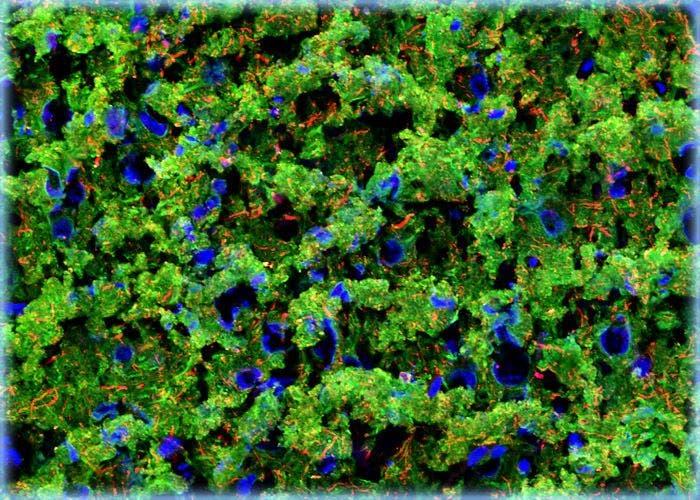

Cerebral Cortex

The cerebral cortex is the outer mantle of the brain that in humans is highly folded. Due to this folding, numerous fissures and crests (termedsulciandgyri) can be seen along the surface of the human brain. The cerebral hemispheres are usually each considered to be divided into six lobes (frontal, parietal, temporal, occipital, central, and limbic lobes) based upon the location of particular sulci and gyri, which vary little between individuals.